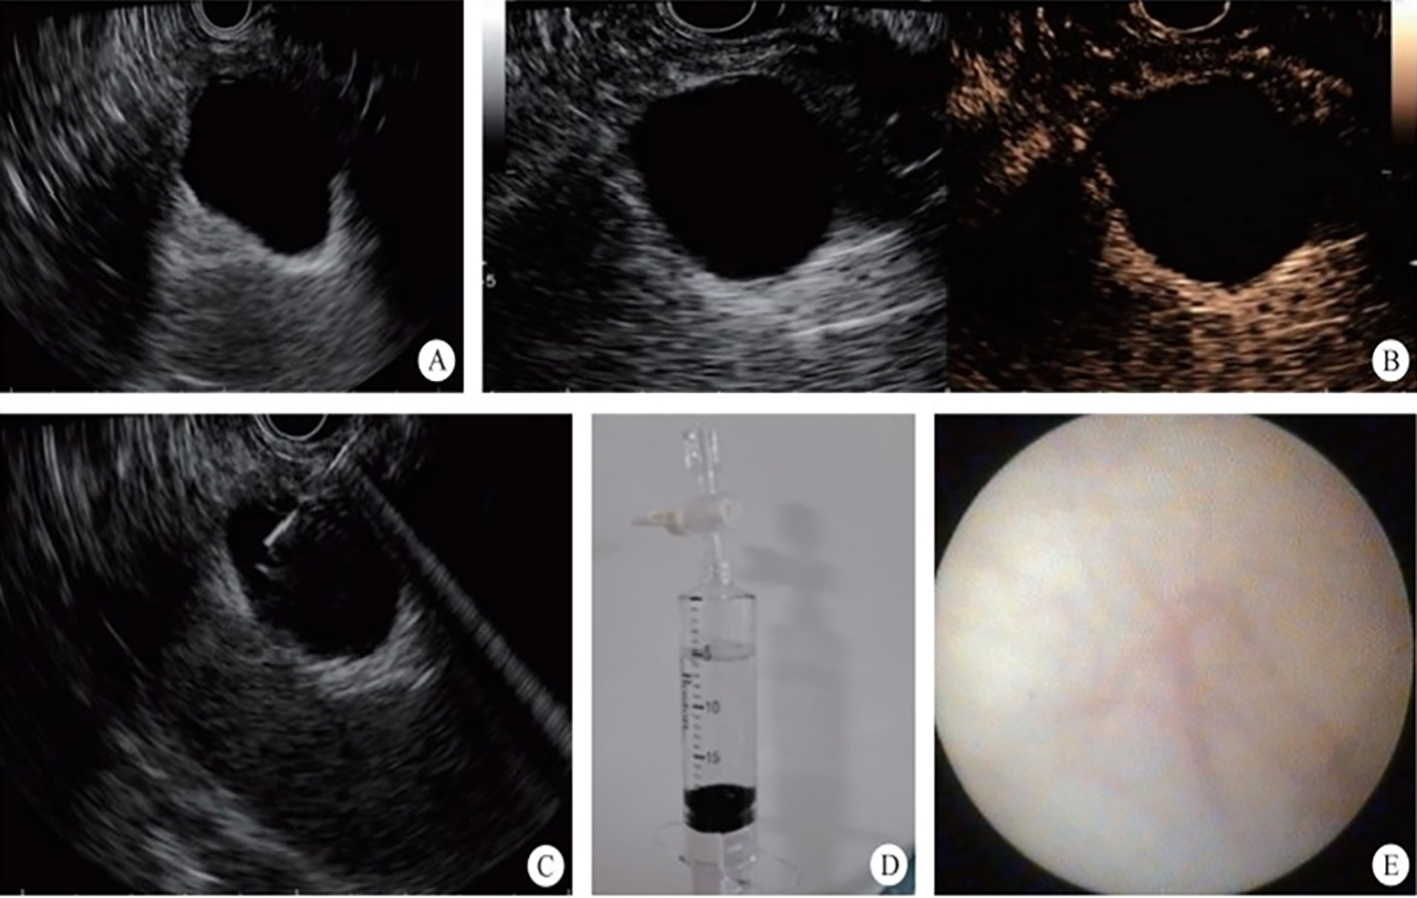

3. Development of the puncture channel. Over the past 10 years, endoscopic ultrasonography (EUS) has gradually become the third eye for endoscopists. Its combination with SMIS brings a new type model for the diagnosis and treatment of organic lesions outside the digestive tubes. For example, EUS-guided bile drainage (EUS–BD) and EUS-guided pancreatic duct drainage (EUS–PD) have been used as effective treatments after the failure of trans-nipple drainage; meanwhile the treatment strategy for acute necrotizing pancreatitis has also changed greatly. EUS-guided super minimally invasive drainage by gastric parietal puncture for pancreatic encapsulated necrosis and EUS-guided pancreatic cystic lesion puncture laurosinol ablation have become the mainstream treatment methods. In the future, SIMS operations like exploring and refining super minimally invasive drainage via a gastric puncture channel for suppurative cholecystitis, EUS-guided super minimally invasive gallstone extraction via a gastric puncture channel, EUS-guided portosystemic shunts and EUS-guided drainage of the chest, the abdomen and pelvic abscess, etc. will be the development directions.

FIG. 2.3 — SMIS through a puncture channel.